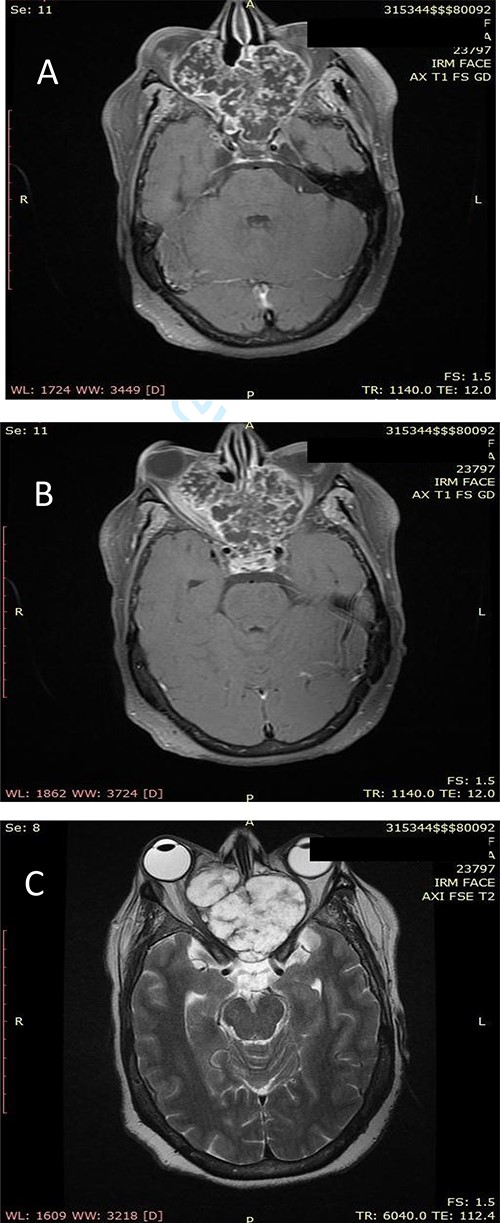

Our patient was a 55-year-old woman, without significant pathological history, presenting a right cheek swelling evolving over 1 year, with unilateral right nasal obstruction gradually becoming bilateral which was associated with a hyposmia, a bilateral exophthalmos, decrease bilateral deep visual acuity and intense permanent frontal headaches that were resistant to the usual analgesics. The clinical examination found a straight cheek and fixed painful mass of firm consistency, with irregular contours. The nasal flow was abolished on the right side and reduced on the left. Nasal endoscopy revealed a budding tumor process obstructing the two nasal cavities, without bleeding and it was masked by purulent secretions. Craniofacial computed tomography (CT) scan showed a large tumor process in the center of the nasosinusal region containing peripheral and central popcorn calcifications, with irregular contours, weakly enhancing after injection of contrast product and measuring ~65 × 62 mm (Fig. 1A–C; see Supplementary Material 1 for a detailed description). Magnetic resonance imaging (MRI) showed a lobulated, heterogeneous tissue process, hyperintense in T2, hypointense in T1. This tumor had a heterogeneous enhancement after injection of Gadolinium and measured 61 × 60 mm. It was also centering on the nasal cavities and on the ethmoid cells that caused lysis of the nasal turbinates and invaded the riddled blades of the ethmoid and with intra-orbital extension bilaterally (Fig. 2A–C; see Supplementary Material 1 for a detailed description). The histopathological analysis of the biopsy specimens found chondrosarcoma. An additional imaging based on thoraco-abdominal-pelvic CT scan did not show other locations. The patient underwent an endoscopic endonasal surgery that was incomplete due to the extension to the orbit and the brain (Fig. 3). The histopathologial analysis of the resected specimens confirmed the diagnosis of grade 2 chondrosarcoma (Fig. 4A and B). Our patient received adjuvant radiotherapy using a total dose of 50 Gy. After 6 months, post-therapeutic imaging based on CT and MRI showed a significant and clear decrease of the tumor volume with persistent residual tumor at the base of the skull given the incomplete excision. With a follow-up of 9 months, there was no recurrence.

(A) Axial facial MRI in T1 sequence after Gadolinium injection showing a lobulated tissue process, occupying the nasal cavities, enhancing heterogeneous. (B) Axial facial MRI in T1 sequence after Gadolinium injection showing bilateral exophthalmos and a mass effect on the optic nerves. (C) Axial facial MRI in T2 sequence showing endocranial extension opposite the frontal lobes.